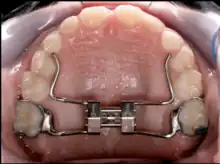

Rapid palatal expansion (RPE) or Rapid Maxillary Expansion (RME) is an expansion technique where expansion of 0.5 mm to 1 mm is achieved each day until the posterior crossbite is relieved. The expander works by turning a key inside the center of the expander. The turn of this key will push the arms of the expander.

For stability purposes, the RPE usually remain in the patient's mouth anywhere between 3–6 months, but this time may vary between patients. This is often known as "six month retention period" during which the bone fills the gap in the maxilla that was created by the expansion process. To prevent any type of relapse, a retainer is given to the patient to keep the teeth in proper alignment.[6] RPE can be tooth supported, bone supported or both.